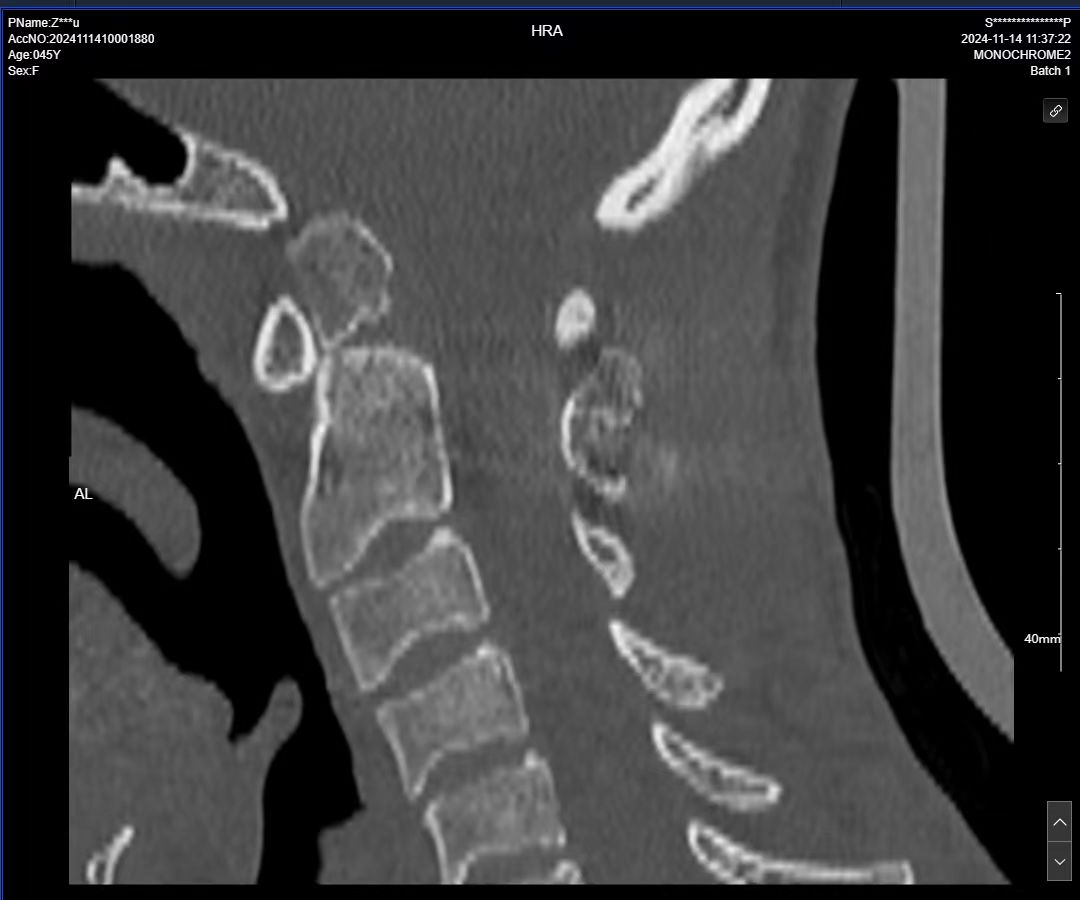

• 术后影像:

• 2024.11.07,复查,对位良好。